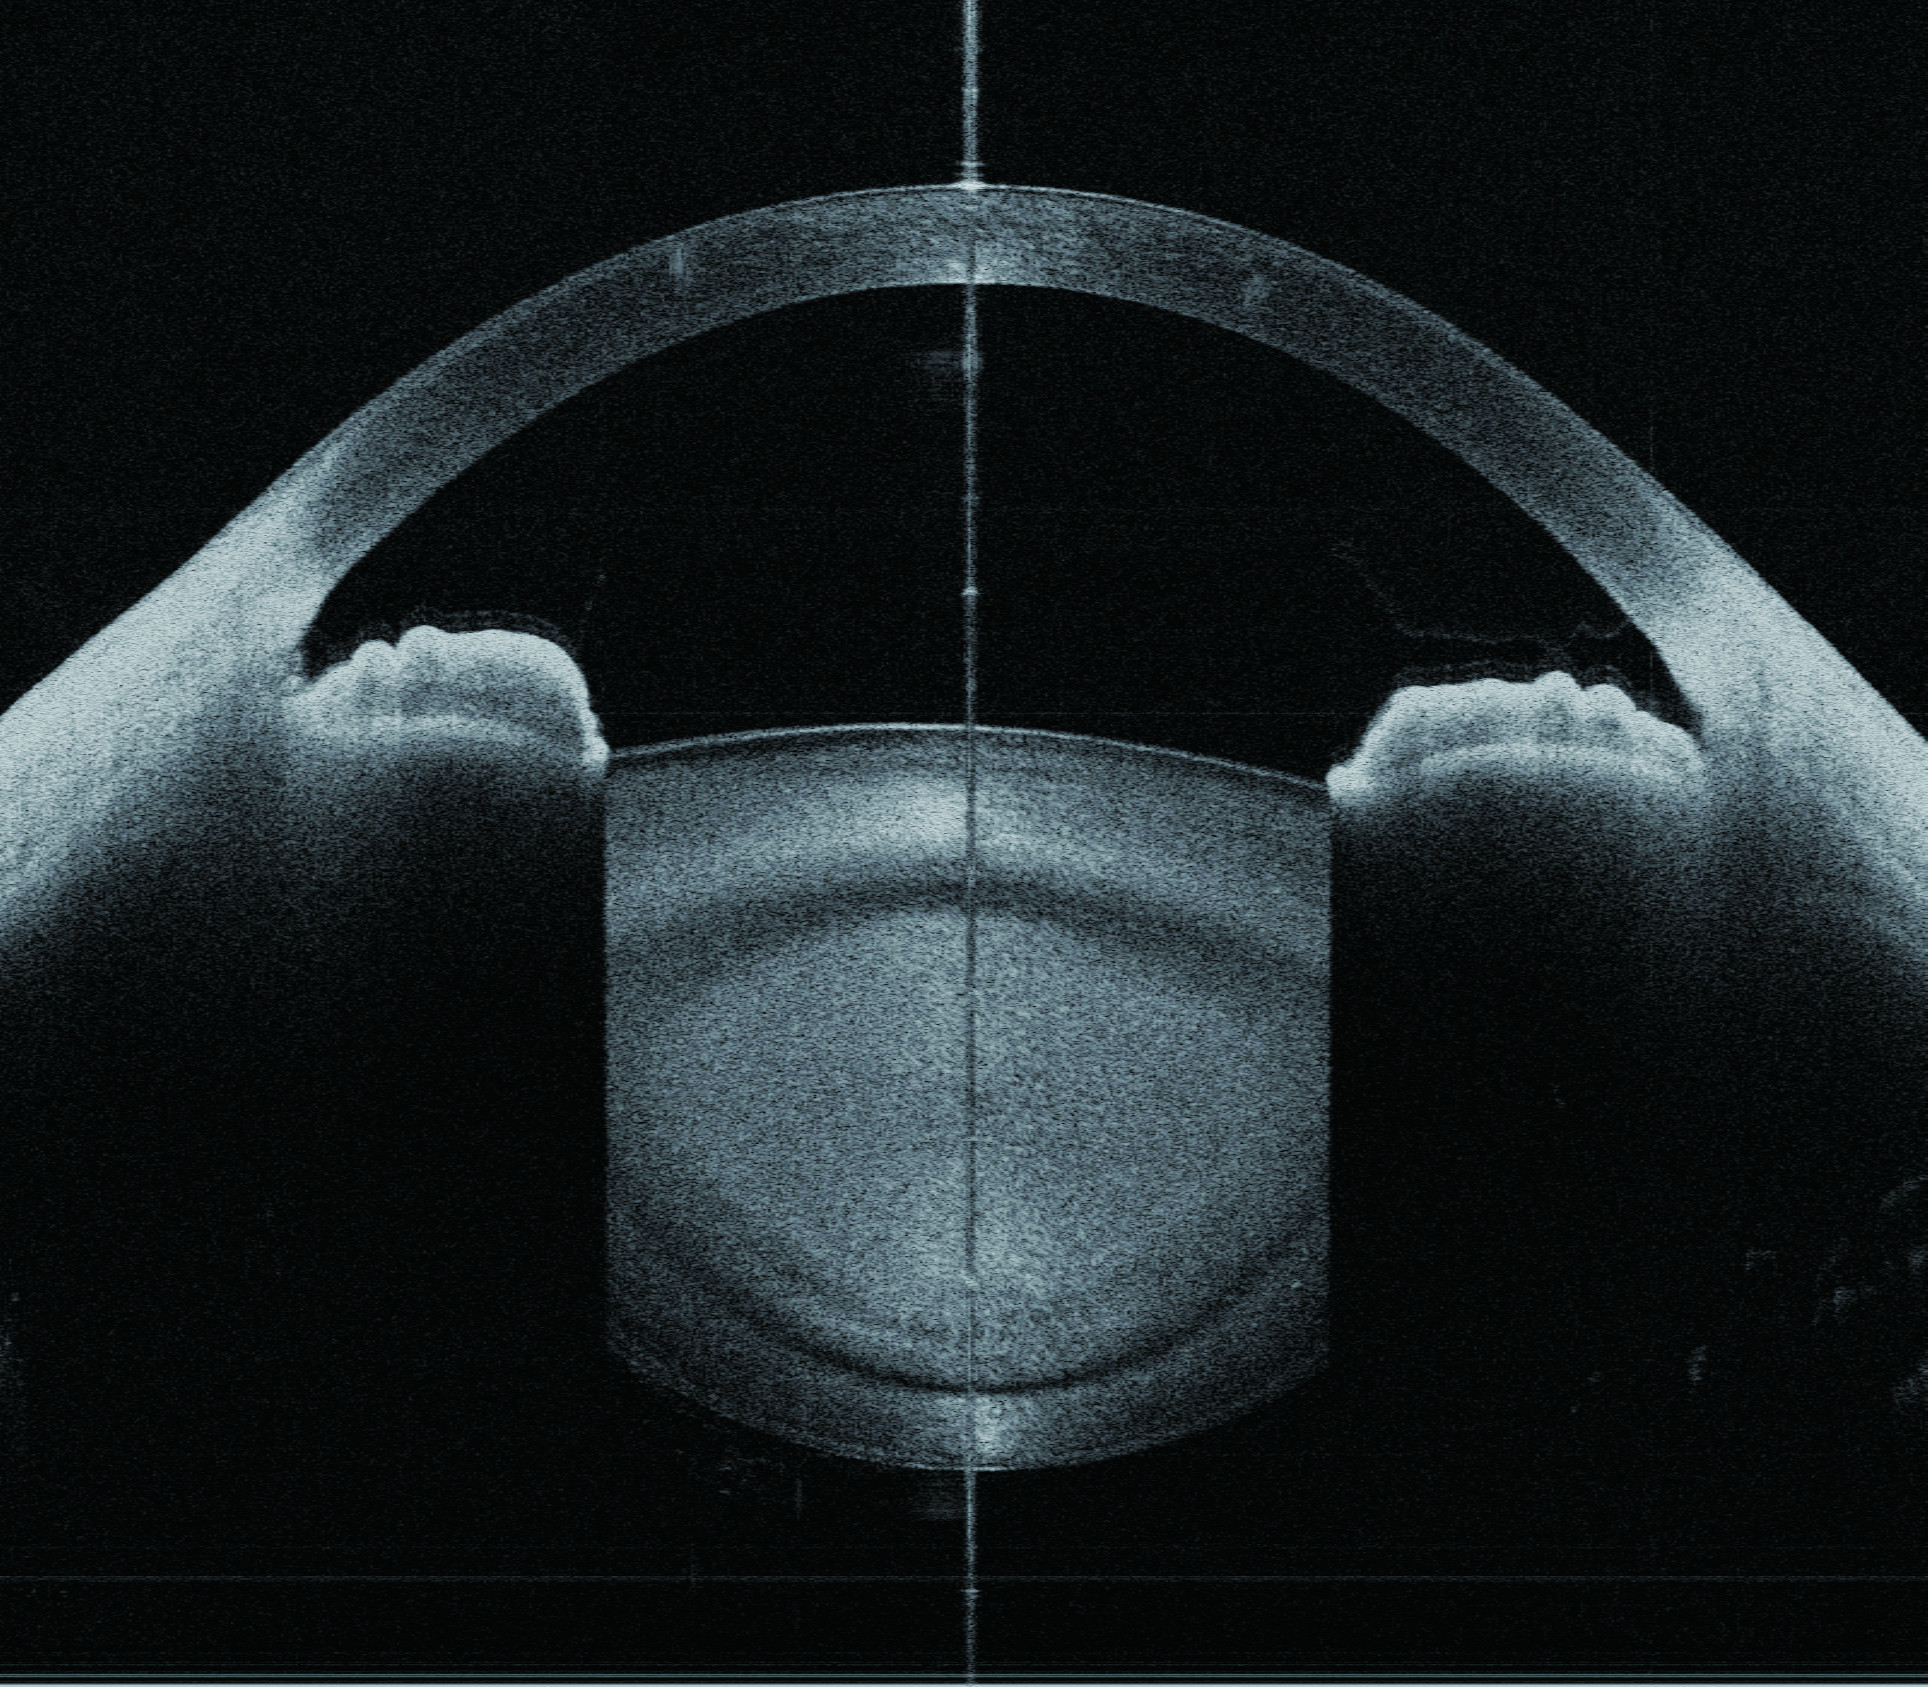

Glaucoom

Met onze STAR 360°-applicatie meet de CASIA2 automatisch alle hoeken van de voorste oogkamer rondom het voorste segment dankzij de automatische detectie van sclerale sporen en biedt u alle gedetailleerde parameters voor een ideale glaucoomdiagnose.